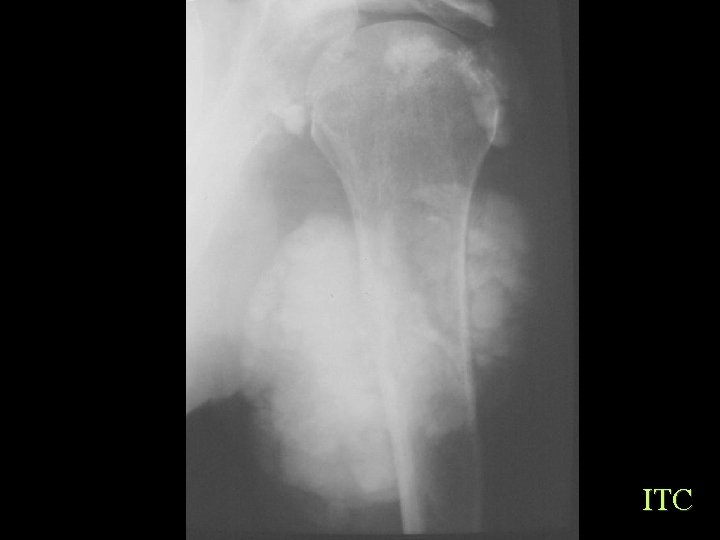

Soft Tissue Calcification By Cause Generalized Calcinosis Idiopathic Tumoral Calcinosis • • 10 -30 Yrs, black Elevated phosphate Single or multiple firm tumour like painless Hips, Shoulders, Elbows, Ankles Dense, Flocculent, Amorphous, 1 -20 cm, fluid levels Dx of exclusion

ITC